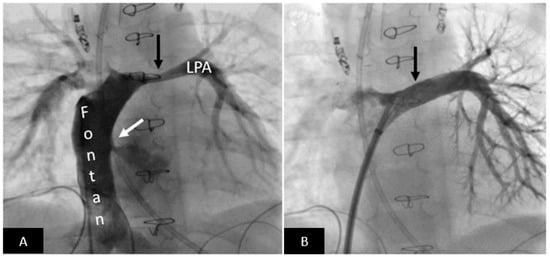

2.2. Endovascular Stenting of Obstructed Blood Vessels

- Acute risks include access site vascular injury, stent migration, implantation site vascular injury, need for emergency surgery, compression of adjacent vascular structures (coronary artery compression during right ventricular outflow stenting or the airway, left bronchial compression during left pulmonary artery stenting after Fontan palliation), and rarely death.